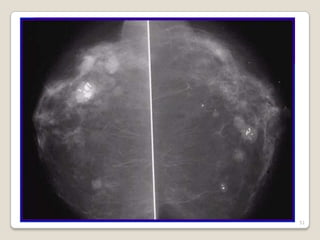

 > Incidencia entre 30 y 40 años

 Más común en: nulíparas, menarca

precoz, menopausia tardía y ciclos

irregulares.

 Por lo general es bilateral con propensión

hacia cuandrante superoexterno.

 Manifestaciones clínicas: áreas palpables

de fibrosis y quistes en mama. Pacientes

se quejan de dolor y sensación de

plenitud.

Cambios Fibroquisticos

Ocurren en tres etapas:

 Fase temprana: 3ra década. El tejido

mamario se torna grumoso, aumenta el dolor

y recidiva después de la menstruación.

 Segunda fase: 4ta década. Se acentúan dolor

y sensibilidad. Aumentan las áreas quísticas.

Los síntomas se resuelven después del ciclo.

 Tercera fase: 5ta década. Múltiples masas

quísticas persistentes

 Etiopatogenia: se desconoce causa

exacta. Exceso de estrógenos o

deficiencia de progestágenos ???

 Tx:

Objetivo detener el progreso y aliviar.

Vit. E, ACOS, Danazol, Bromocriptina,

Tamoxifeno

Pacientes con macroquiste: Tx. Quirúrgico